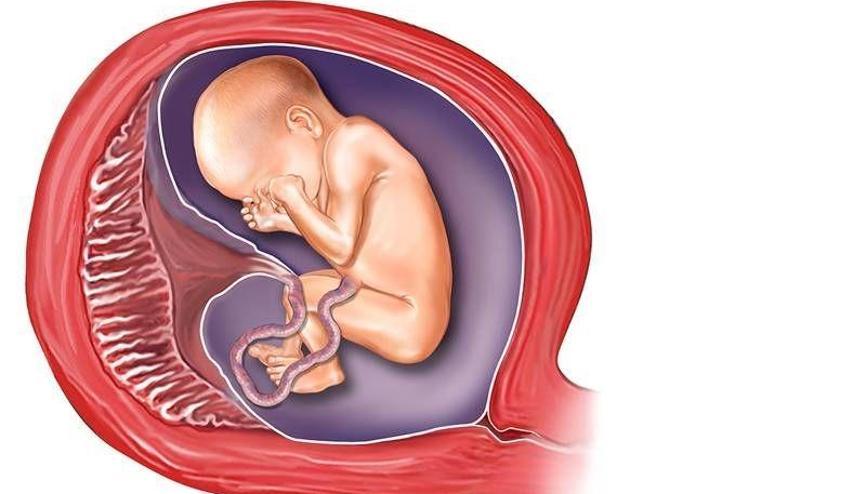

Амнион и Околоплодные Воды: Функции и Роль в Беременности